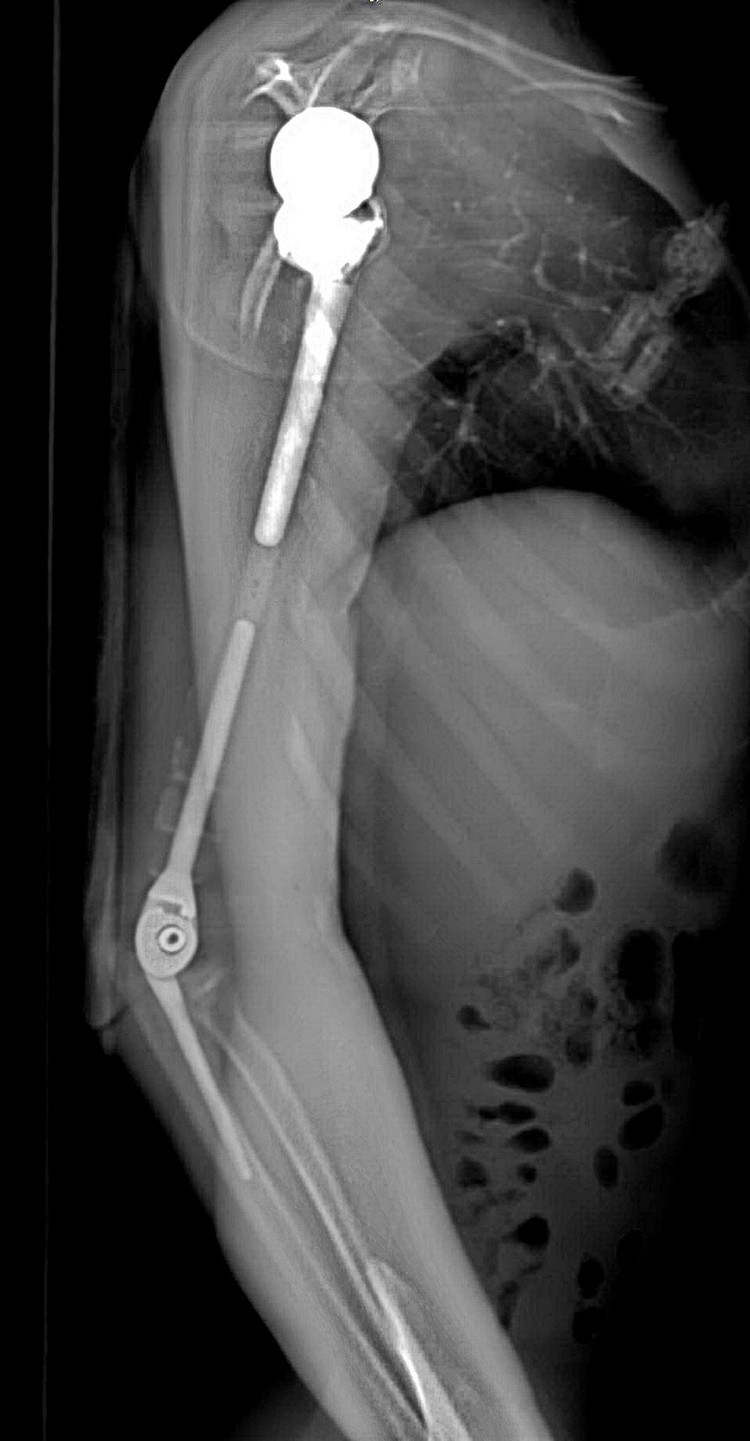

Ảnh chụp X-quang tay phải của bệnh nhân sau khi phẫu thuật thay xương toàn bộ cánh tay

Nhóm phẫu thuật đã lên kế hoạch sử dụng các công nghệ trong tái tạo xương hiện đại nhất hiện nay bao gồm tái tạo lại cấu trúc khớp vai, cấu trúc khớp khuỷu bằng vật liệu hợp kim titan. Đặc biệt, đội ngũ bác sĩ của Trung tâm đã có một quyết định định táo bạo: không sử dụng hoàn toàn vật liệu kim loại mà chế tạo phần thân xương cánh tay sử dụng công nghệ in 3D vật liệu polyme sinh học (PEEK). Vật liệu này do phòng nghiên cứu ứng dụng công nghệ in 3D của Đại học VinUni sản xuất, giúp kết nối phần khớp vai và khớp khuỷu với nhau, đồng thời phục hồi lại điểm bám của các gân cơ quanh cánh tay. Đây được coi là một quyết định đầy tính sáng tạo dựa trên những nghiên cứu và thử nghiệm chuyên sâu từ nhiều ca bệnh đã thành công của ê-kíp phẫu thuật.

Ảnh chụp X-quang so sánh xương cánh tay 2 bên sau khi phẫu thuật

Đặc biệt, công nghệ in 3D được coi là công nghệ duy nhất hiện nay mang lại khả năng cá thể hóa các chi tiết cấy ghép. Nhờ công nghệ này, cả 3 phần của xương cánh tay nhân tạo đều được “thiết kế riêng” theo đúng kích thước cánh tay thật của bệnh nhân, đồng thời có các điểm cố định giúp khôi phục lại hệ thống gân cơ bám xương. Trước khi sản xuất, tất cả những thiết kế này đều được thử nghiệm mô phỏng khả năng vận động, chịu lực trên máy tính. Nhờ vậy, xương nhân tạo sau ghép sẽ tương thích tối đa, “hoàn toàn vừa vặn” với cơ thể người bệnh và thời gian phục hồi chức năng vận động của cánh tay sẽ được rút ngắn đáng kể.